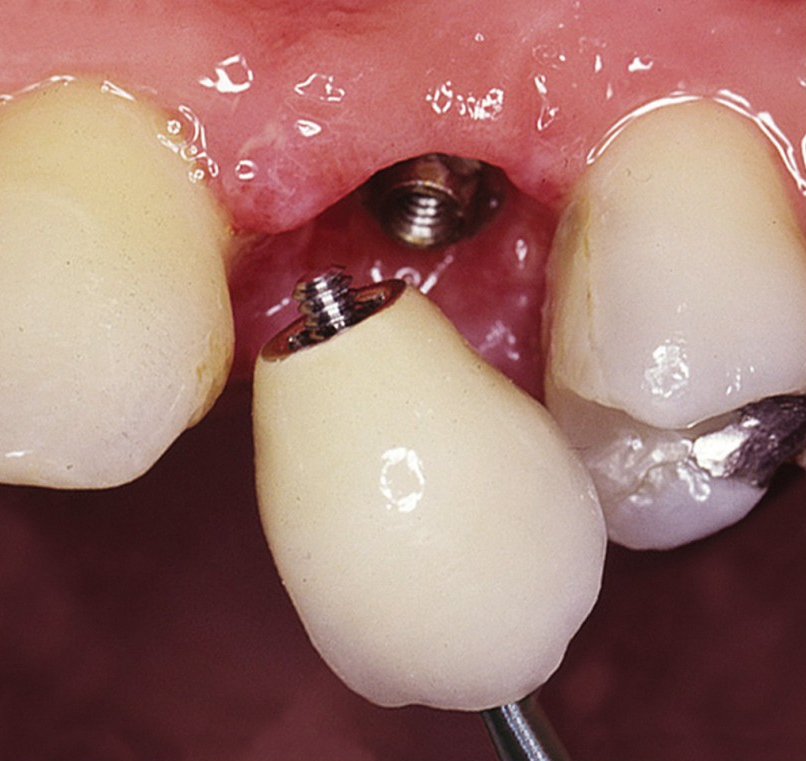

• Otisk situace v ústech a vytvoření modelu v laboratoři

• Zkouška zubní náhrady

• Předání definitivní náhrady

V zásadě je možné do těchto můstků zařadit i přirozené zuby, zejména pokud je potřeba tyto zuby ošetřit proteticky – korunkami. Korunky nebo můstky mohou být na implantáty nacementovány nebo přišroubovány.

Pevné můstky – lepené nebo šroubované